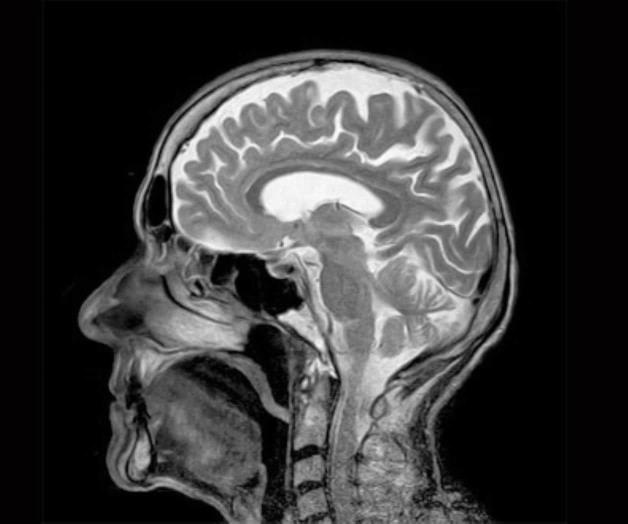

El abanico de conductas es amplio, pero todos los psicópatas coinciden en una cosa: las alteraciones cerebrales que los diferencian de otros individuos sin este trastorno. Pujol y su equipo revisaron más de 400 artículos científicos en los que se había analizado el cerebro de las personas con psicopatía a través de resonancias magnéticas. El metaanálisis, publicado en la revista científica Psychological Medicine, ha concluido que el cerebro de los psicópatas presenta una maduración acelerada de varias regiones cerebrales relacionadas con el procesamiento emocional y el cognitivo. "El cerebro de los psicópatas es diferente desde el punto de vista anatómico y funcional. Hay diferencias en las áreas que procesan la cognición y el razonamiento y en las que procesan la actividad emocional. La conexión entre estas dos áreas falla", explica Pujol.

Los investigadores encontraron que, desde el punto de vista anatómico, en las regiones de lóbulo temporal (donde está la amígdala, relacionada con la emociones) y en el frontal (encargado de las funciones cognitivas) había "una aparente atrofia de la sustancia gris". "Sin embargo, lo que luego nosotros postulamos es que, en realidad, lo que había era un aumento de la sustancia blanca, lo que implica una sobremaduración de esas áreas", apunta Pujol.